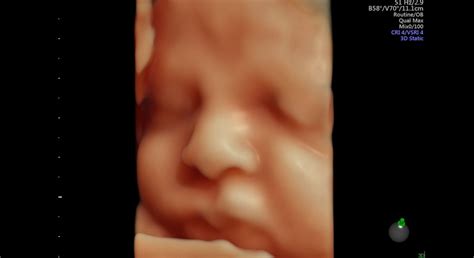

V brušku má už bábätko naozaj málo miesta a priestoru na pohyb nemá veľa. Plod má v brušku naozaj tesný priestor. Aj to je jasný signál, že plod z malého zrniečka maku dozrel do zjavu malého novorodenca. Bábätko naďalej rastie, no viac už priberá. Stále si cmúľa prsty, trénuje si tak sací reflex. Veľmi dobre vníma zvuky, melódie a počúva upokojujúci tlkot mamičkinho srdiečka. Pľúca sú už vyvinuté natoľko, že dokážu fungovať aj mimo maternice. Všetko si bábätko natrénovalo pri prehĺtaní a vdychovaní plodovej vody. V tele bábätka sa produkuje kortizol, vďaka čomu pľúca správne dozrievajú. Kosti spevneli, no sú dostatočne flexibilné, aby sa prispôsobili pôrodným cestám. Imunitný systém sa ďalej vyvíja. Väčšinu protilátok získava plod od matky. Čím viac času bábätko v brušku strávi, tým bude imunita lepšia. Pečeň je vyvinutá a odvádza odpadové látky. Mozog je neustále aktívny, čo dieťatku pomáha neustále zdokonaľovať funkčnosť procesov v organizme. Srdiečko a obehový systém sú plne funkčné. Frekvencia oziev je približne 120 až 160 úderov za minútu. V tomto období sa u dieťaťa striedajú kratšie a dlhšie intervaly spánku a bdenia. Tieto cykly sú pomerne individuálne. Približne 30 % času trávi pokojným spánkom a 60 % aktívnym spánkom, v ktorom môže hýbať očami a končatinami.

V 37. týždni tehotenstva má bábätko približne 49 cm a jeho hmotnosť stúpla asi na 3000 g. Veľkosť plodu je od hlavy po päty 47 až 54 cm. Dieťatko je už teda približne také veľké, ako keď príde na svet. Váha dieťaťa v 37. týždni tehotenstva variuje niekde medzi 2 800 až 3 100 kg.

Na hlave má asi 2,5 cm dlhé vlásky. Maternica je dieťatku už naozaj tesná, v „poskladanej“ pozícii sa však aj tak snaží v rámci možností pohybovať. Dieťa meria od temena po zadoček asi 35 cm a váži necelé 3 kg.